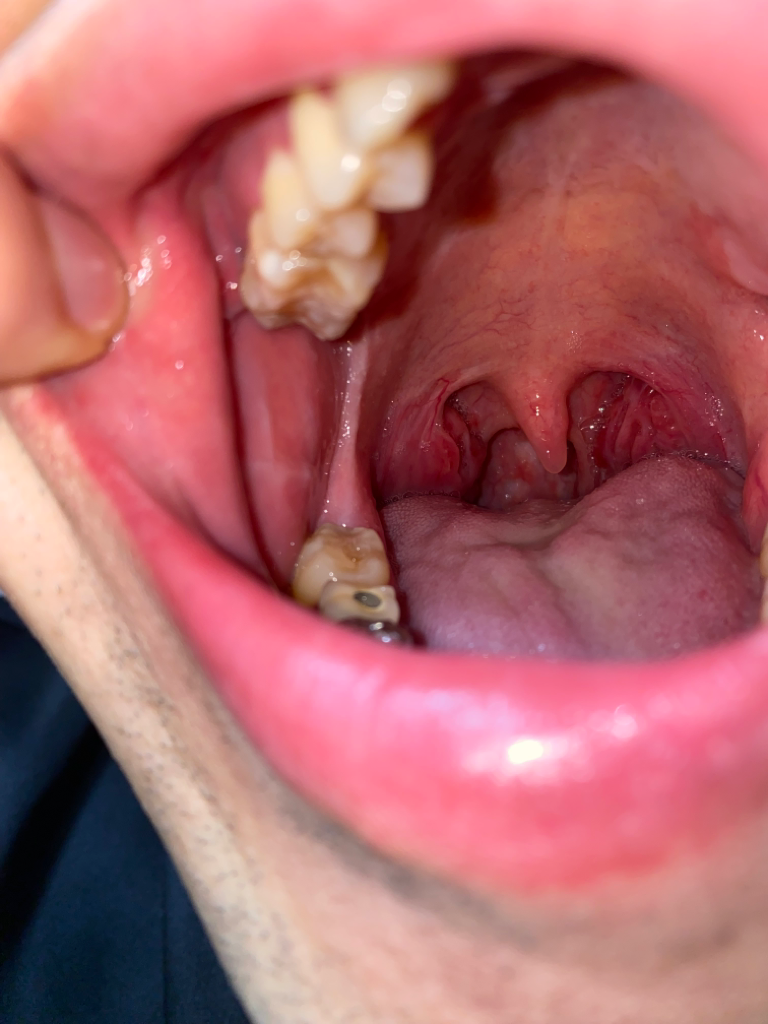

아침 양치할때와 식사후에 침에 피가 섞여 나온지 엄청 오래돼서 코, 목, 폐 등 다 검사를 받았는데 이상이 없다고 합니다. 그러다 거울을 보는데 편도쪽이 헐어서 피같은게 보이고 오른쪽(사진상에서는 왼쪽) 볼과 윗 어금니와 아래 어금니 연결된 부분(후구치 삼각 부분)이 하얗게 상처난듯이 모양과 색이 변해있었습니다. 이것도 꽤 오래 됐어요 한 1년? 평소에 볼을 자주 씹습니다 ㅠ 그리고 오른쪽 편도쪽으로 통증 있고 자극적인 음식 먹으면 작열감도 생깁니다 ㅜ

혹시 구강암일까요?? 어제 대학병원에서 코쪽 내시경과 머리ct 찍었는데 이상 없었습니다 ㅠ

귀하의 경우, 입 안 오른쪽 볼과 후구치 삼각 부분이 하얗게 변하고, 침에 피가 섞여 나오는 증상이 있으므로, 구강암의 가능성을 배제할 수 없습니다.

그러나, 귀하는 이미 코, 목, 폐 등 구강암이 발생할 수 있는 다른 부위에 대한 검사를 받았고, 이상이 없다고 하셨습니다. 또한, 대학병원에서 코쪽 내시경과 머리 CT를 찍었지만, 이상이 없었다고 하셨습니다.